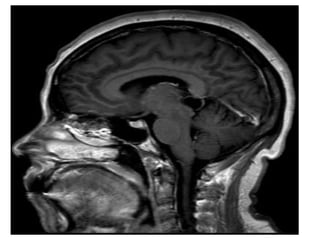

a) Incidence :

-Tectal plate gliomas are encountered in

children and adolescents

-Usually low grade tectal tumor causing

aqueduct stenosis

-Typically low grade astrocytoma with good

prognosis

b) Radiographic Features :

-CT :

-Typical CT finding is homogenous expansion of

tectal plate, isodense to grey matter with

minimal enhancement in postcontrast image

CT shows non-communicating hydrocephalus , note the low density lesion of

the tectal plate

-MRI :

-Typically the tumors demonstrate expansion of the

tectal plate by a solid nodule of tissue

*T1 :

-Iso to slightly hypointense to grey matter

*T2 :

-Hyperintense to grey matter

*T1+C :

-Usually no enhancement

-Higher grade tumors tend to be larger and tend to

enhance more vividly